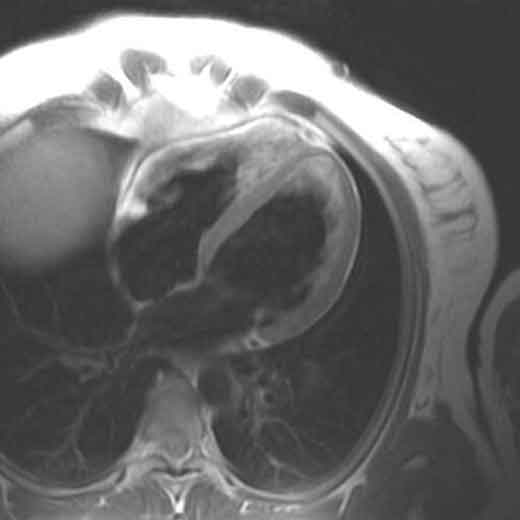

Cho ha isolato un segmento di midollo spinale di porcellino d’India, ne ha compressa una sezione e ha applicato la chitina modificata e aggiunto un colorante fluorescente in grado di penetrare attraverso le membrane cellulari danneggiate. Con tale accorgimento il tessuto del midollo spinale si sarebbe colorato se e solo se il chitosano non fosse stato in grado di riparare il danno. Nell’osservazione al microscopio, Cho ha potuto riscontrare con sorpresa che il midollo spinale era immacolato.

In seguito Cho ha verificato la capacità del chitosano di impedire la fuoriuscita dalle cellule del midollo spinale, sorprendendosi di osservare come il livello di fuoriuscita dell’enzima di dimensioni enormi lattato deidrogenasi fosse addirittura inferiore a quello del midollo spinale non danneggiato: lo zucchero aveva evidentemente riparato le membrane non solo nel sito di compressione ma anche in altri punti in cui le membrane cellulari erano state rotte dal maneggiamento.